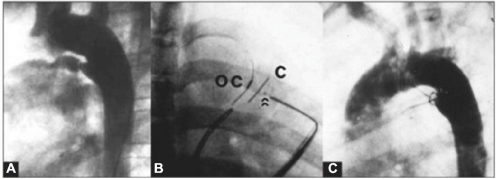

Na figura abaixo, observa-se uma oclusão de ducto arterioso. A: Canal arterial tipo A de 2 mm (milímetros) de diâmetro; B: Configuração helicoidal do dispositivo com uma alça na artéria pulmonar e duas alças na ampola aórtica; C: A ortografia de controle, evidenciando oclusão total.

Qual alternativa apresenta o dispositivo de oclusão utilizado.

Na figura abaixo, observa-se uma oclusão de canal arterial. A: Canal arterial calibroso do tipo D; B: A imagem em oblíqua anterior direita mostra o dispositivo abotoado antes da liberação. As setas indicam o botão do oclusor abotoado no contra-oclusor; C: Aortografia de controle, demonstrando ausência de fuga residual.